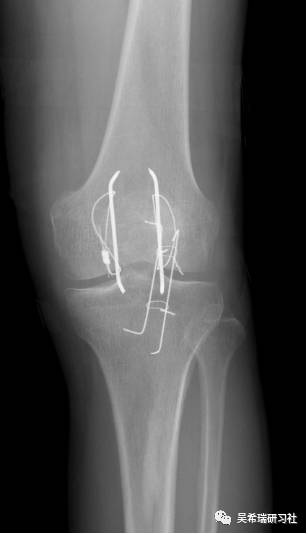

平台骨折手术后继发感染

TIPS:内固定感染常见病不要轻易做皮瓣,感染情况下不可深部骨感染、窦道用水泥切实可行多数皮肤没有缺损,肿胀消退后可以牵张闭合